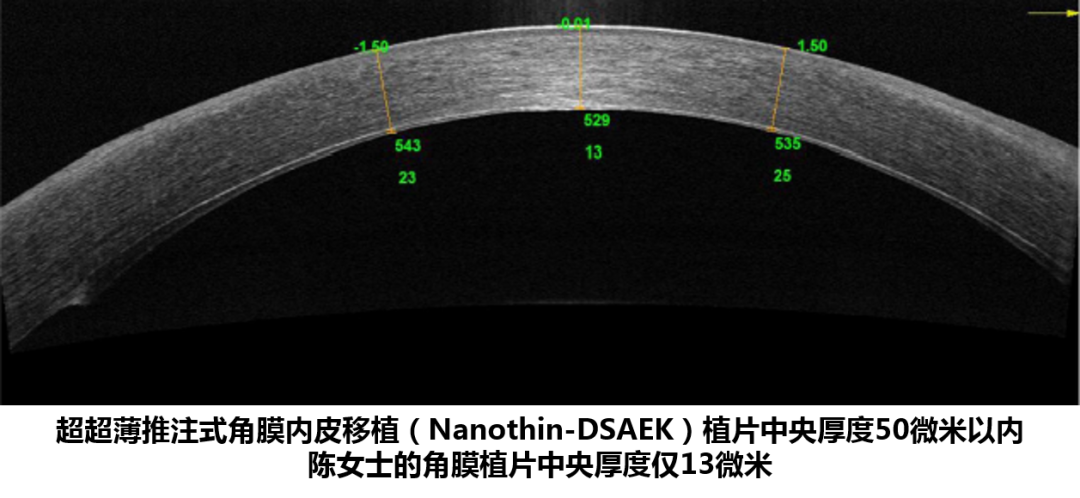

? ? 4月,由溫醫(yī)大眼視光醫(yī)院副院長(zhǎng)、角膜病專家陳蔚教授主刀,為陳女士實(shí)施了全國(guó)首創(chuàng)的“超超薄推注式角膜內(nèi)皮移植術(shù)”。術(shù)后一周她的裸眼視力從原來只能看到30厘米以內(nèi)的手指,上升到了0.5。一個(gè)月后陳女士門診復(fù)查,角膜透明,內(nèi)皮植片貼附良好,測(cè)量植片最薄處僅有13微米,角膜內(nèi)皮細(xì)胞密度為2230個(gè)/mm^2。

? ? ? 全球各角膜移植中心都盡力將DSAEK角膜內(nèi)皮植片中央厚度控制在100微米以內(nèi),這種超薄的植片與常規(guī)植片(中央厚度超過100微米)相比,擁有更好的視覺質(zhì)量。而全球極少數(shù)幾家醫(yī)院在嘗試制備厚度50微米內(nèi)超超薄角膜植片,其術(shù)后視力和DMEK無明顯差異。

據(jù)悉,此次陳蔚教授團(tuán)隊(duì)制備出了中央厚度僅13微米的植片,是目前全球報(bào)道過最薄的DSAEK植片。